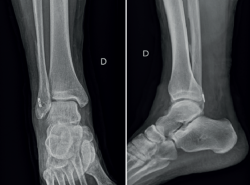

Dado este hallazgo, se realizó un abordaje lateral a la vaina de los tendones peroneos, se incidió en el retináculo y se retiró el dispositivo de fijación. Además, se reparó el tendón peroneus brevis, se hizo una tubulización de este utilizando suturas absorbibles y el retináculo se cerró con suturas absorbibles. La movilidad de los tendones se confirmó como normal, sin signos de subluxación del tendón (Figura 4).

Figura 4. A: dispositivo de fijación rozando la vaina peronea; B: rotura del tendón peroneo corto; C: reparación y tubulización del tendón peroneo corto; D: vaina peronea suturada y cerrada.